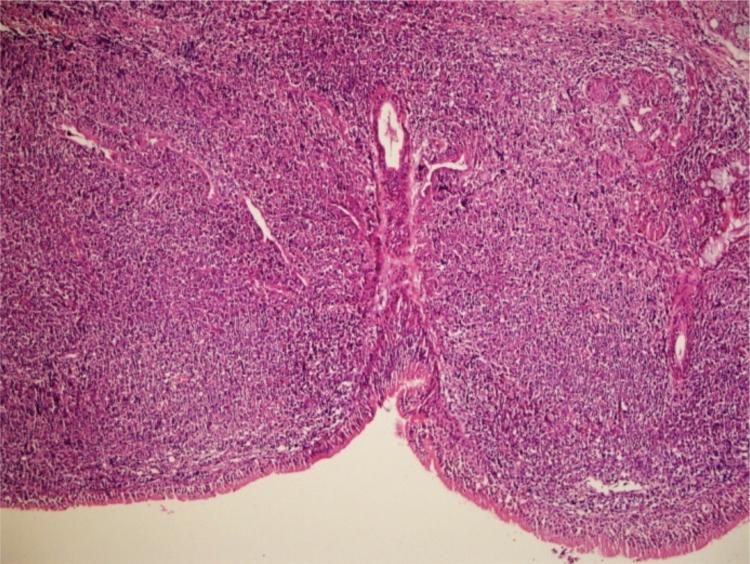

Hoarseness: an unusual presentation of primary thyroid lymphoma with laryngeal infiltration.

Braz J Otorhinolaryngol. 2016 Nov-Dec;82(6):737-740. doi: 10.1016/j.bjorl.2015.05.006. Epub 2015 Sep 7.